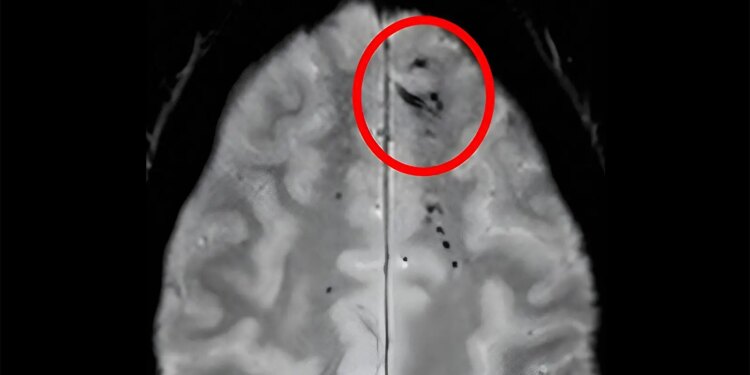

The location and amount of brain microbleeds that a person has could be telling of their risk of dementia, according to an observational analysis.

Cerebral microbleeds, the neuroimaging findings of small blood product deposits, can be considered a sign of cerebral small vessel disease and have previously been associated with dementia and subsequent stroke. Regarding specific microbleed patterns, prior work suggests that microbleeds in the lobar regions and cortical superficial siderosis are consistent with cerebral amyloid angiopathy (CAA), whereas subcortical microbleeds indicate a hypertensive cause.

Participants meeting study criteria came out to 1,583 older adults (mean age 76 years), of whom 22.8% had cerebral microbleeds detected on MRI.